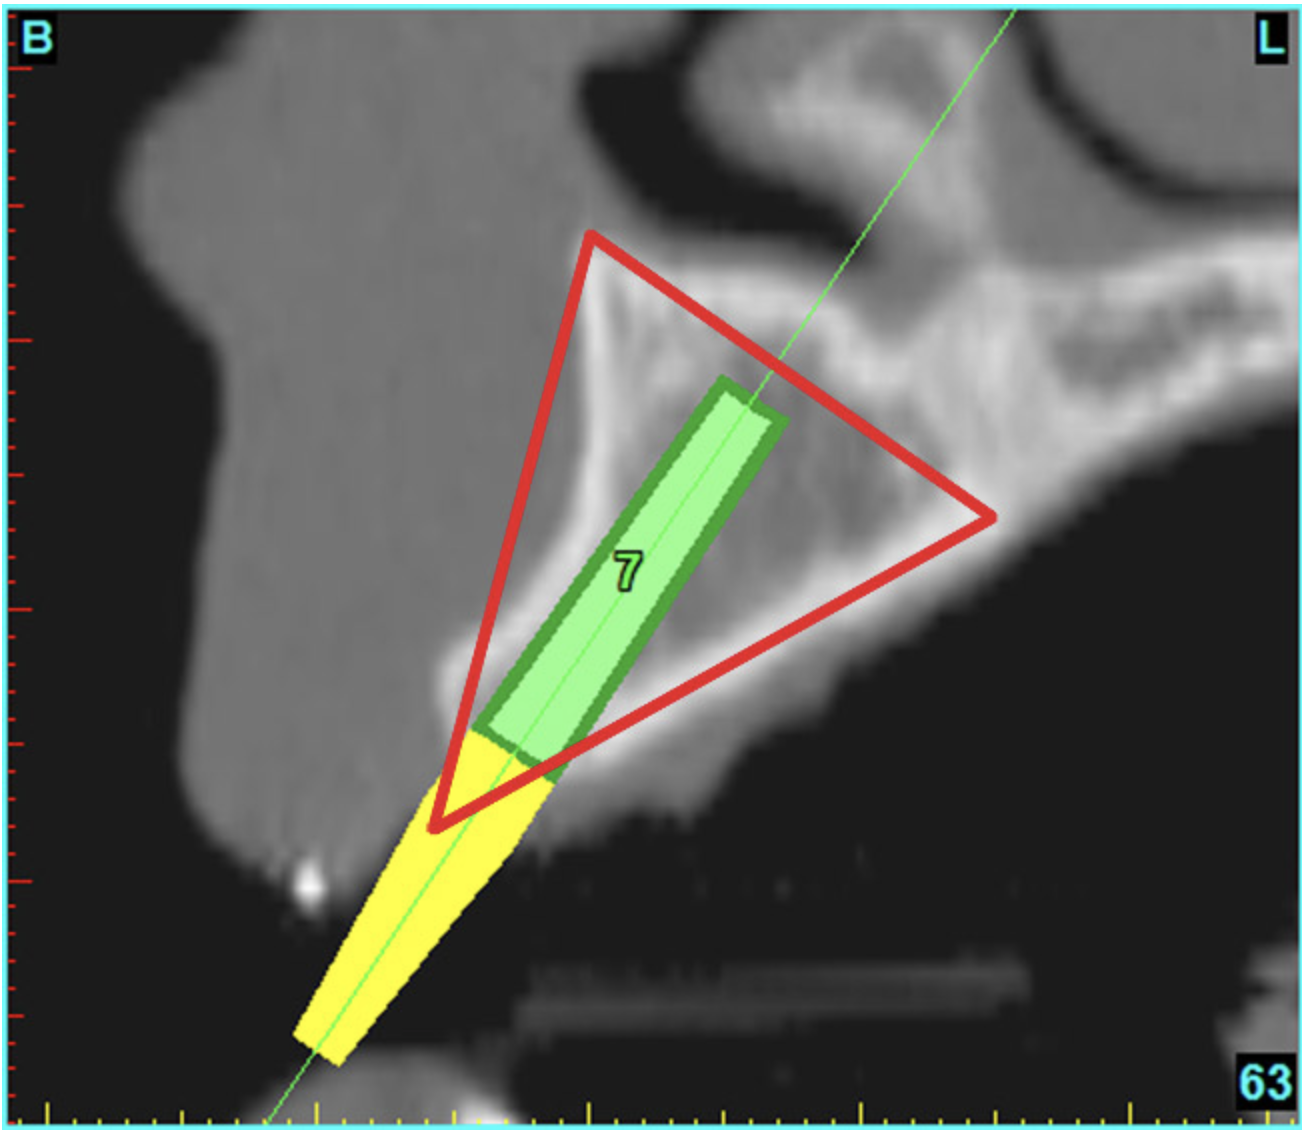

Using the interactive treatment-planning software application, the scan data was assimilated and both potential lateral incisor implant receptor sites were evaluated. It is a combination of the data and the methodology used to interpret the data that is the basis for defining a new paradigm in diagnosis and treatment planning. Proper evaluation of these images and correct use of the interactive treatment-planning software tools is essential in creating a decision tree of treatment options. First, the data from the scan was reformatted into panoramic, axial, and cross-sectional images. The undistorted cross-sectional images revealed the residual alveolar bone in the area of the right lateral incisor. Then, a simulated schematic implant was placed within the bone with an abutment extension to help visualize the connection to the restorative position of the tooth (Figure 4A). The Triangle of Bone® (TOB), a concept developed by the author to analyze bone quality, quantity, and disposition at prospective dental implant sites using CBCT scans, aided in determining available bone volume by defining a “zone” for proper implant placement18,19 (Figure 4B).

After reviewing the CT data and the decision tree, the bone within the “zone” of the TOB was evaluated and found to be satisfactory for implant placement. Because the goal of implant dentistry is not the implant but the tooth that is placed, true restorative-driven implant dentistry must begin with the assumption that the implant position should remain consistent with the tooth it is replacing, and the final implant-supported restoration.12,22-26 The TOB aids the clinician in understanding the link between the implant position and the desired restorative goal. The base of the geometric shaped “zone” is visualized by starting at the widest area of alveolar bone facially and superiorly. The apex of the triangle is positioned to bisect the alveolar crest (Figure 4B). The TOB, the overlay in the cross-sectional image, reveals whether adequate bone is available for implant placement. It also helps to identify concave facial bone defects, and accurately determine the width of bone at the crest. The author recommends using an interactive software application that provides the necessary measurement tools to accurately assess the bone anatomy.

Figure 4b  CT scan data was input into the treatment-planning software, which allowed (A) placement of a simulated implant and (B) the determination of the “zone” for proper placement.

Figure 4b